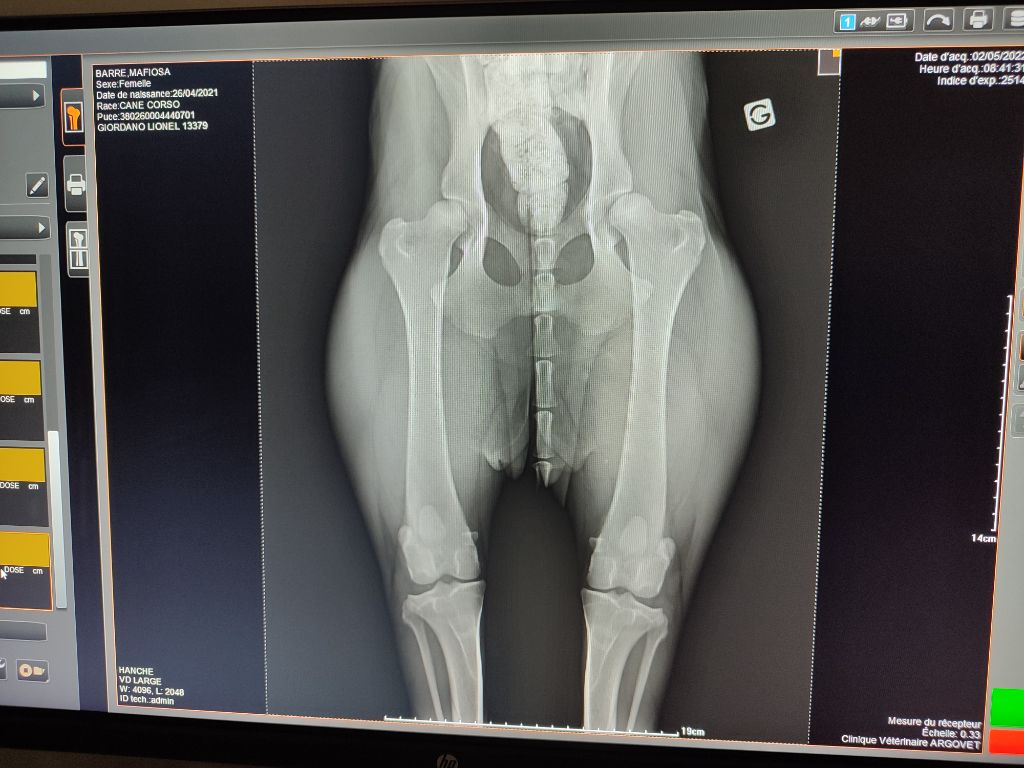

| Couleur | noire ADN HD C / ED 0/ DSRA N/N |